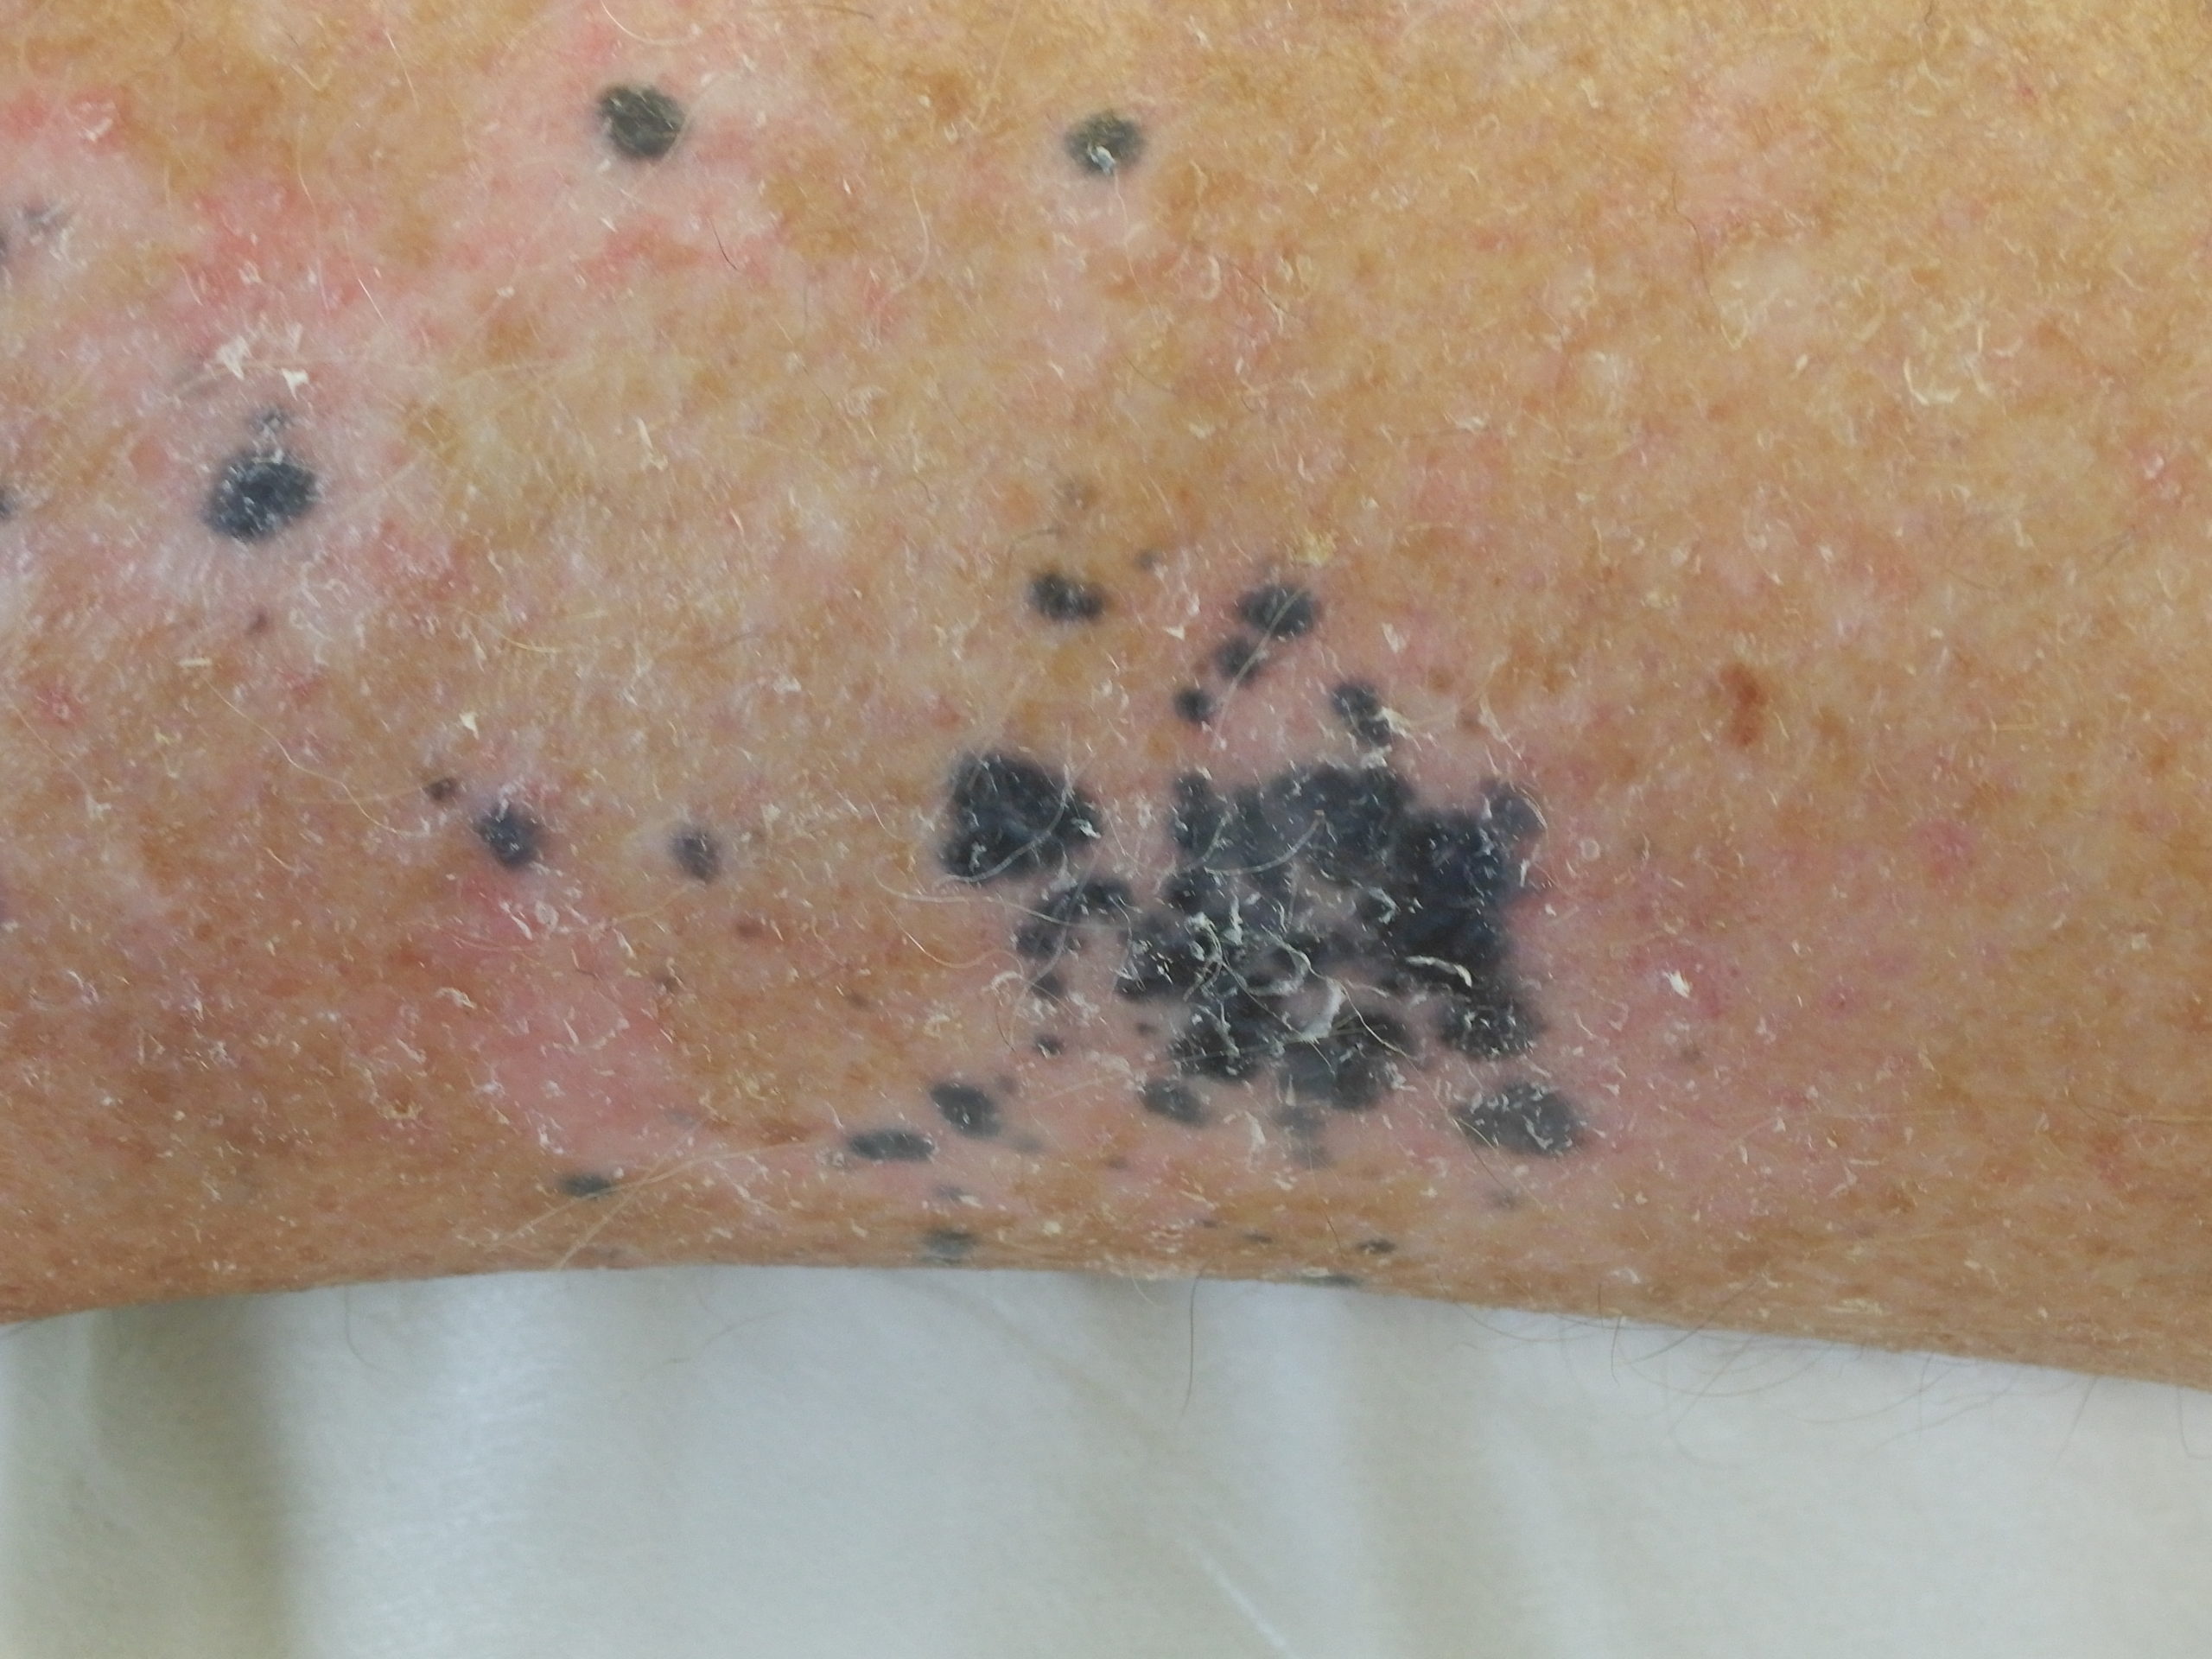

Site: Ankle

Diagnosis: Post Inflammatory Hyperpigmentation

Description: Note the perilesional hypopigmentation

These lesions arose after he went on Check Point inhibitor for metastatic melanoma. Note the perilesional hypopigmentation as well as the post inflammatory hyperpigmentation which was all that was left of his melanoma metastases. These had been stable for the last 9 months with no evidence in PET scans of melanoma elsewhere. This rteally shows the effectiveness of these immune stimulating drugs in metastatic melanoma.